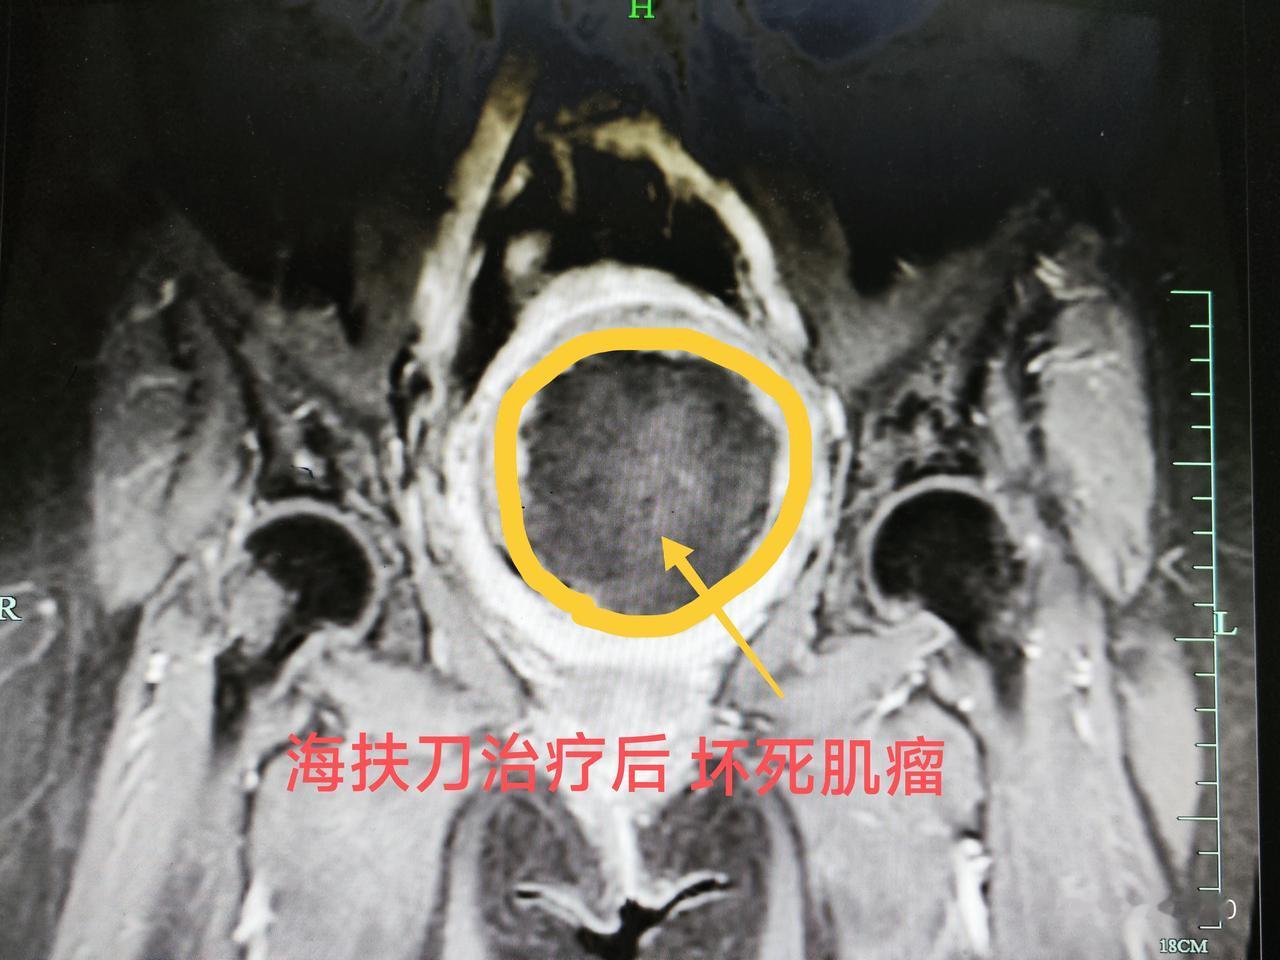

这是来自马来西亚子宫肌瘤患者,病人发现肌瘤十多年,当地建议手术切除,患者不愿意手术一直观察等待和中药治疗,现在肌瘤已经增大到9.5厘米,患者在医生同行那里了解到海扶可以无创消融肌瘤后,专门到我们中心进行治疗,术后复查显示肌瘤消融满意,对内膜也无损伤。子宫肌瘤 海扶刀